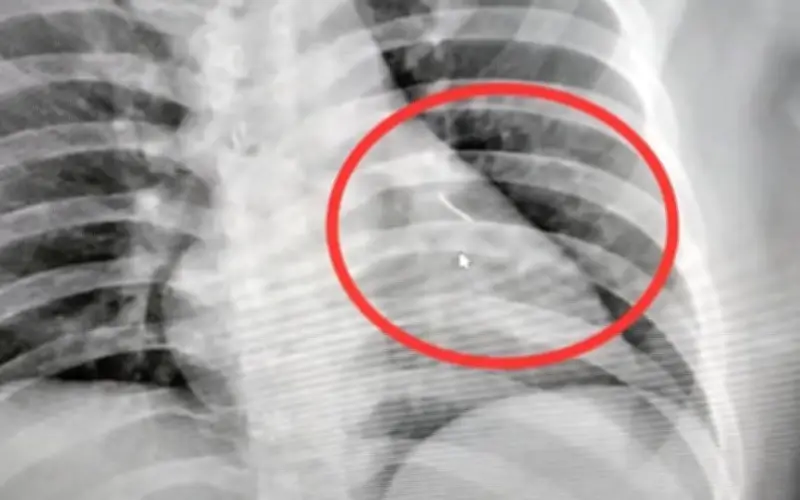

Tại bệnh viện, sau khi chụp X-quang, các nhân viên y tế đã phát hiện một vật thể nhỏ sắc nhọn bên trong cơ thể ông, sau đó được xác định là một cây kim dài khoảng 7 cm. Ông Boonlert lập tức được chuyển đến Bệnh viện Buriram để tiến hành phẫu thuật khẩn cấp.